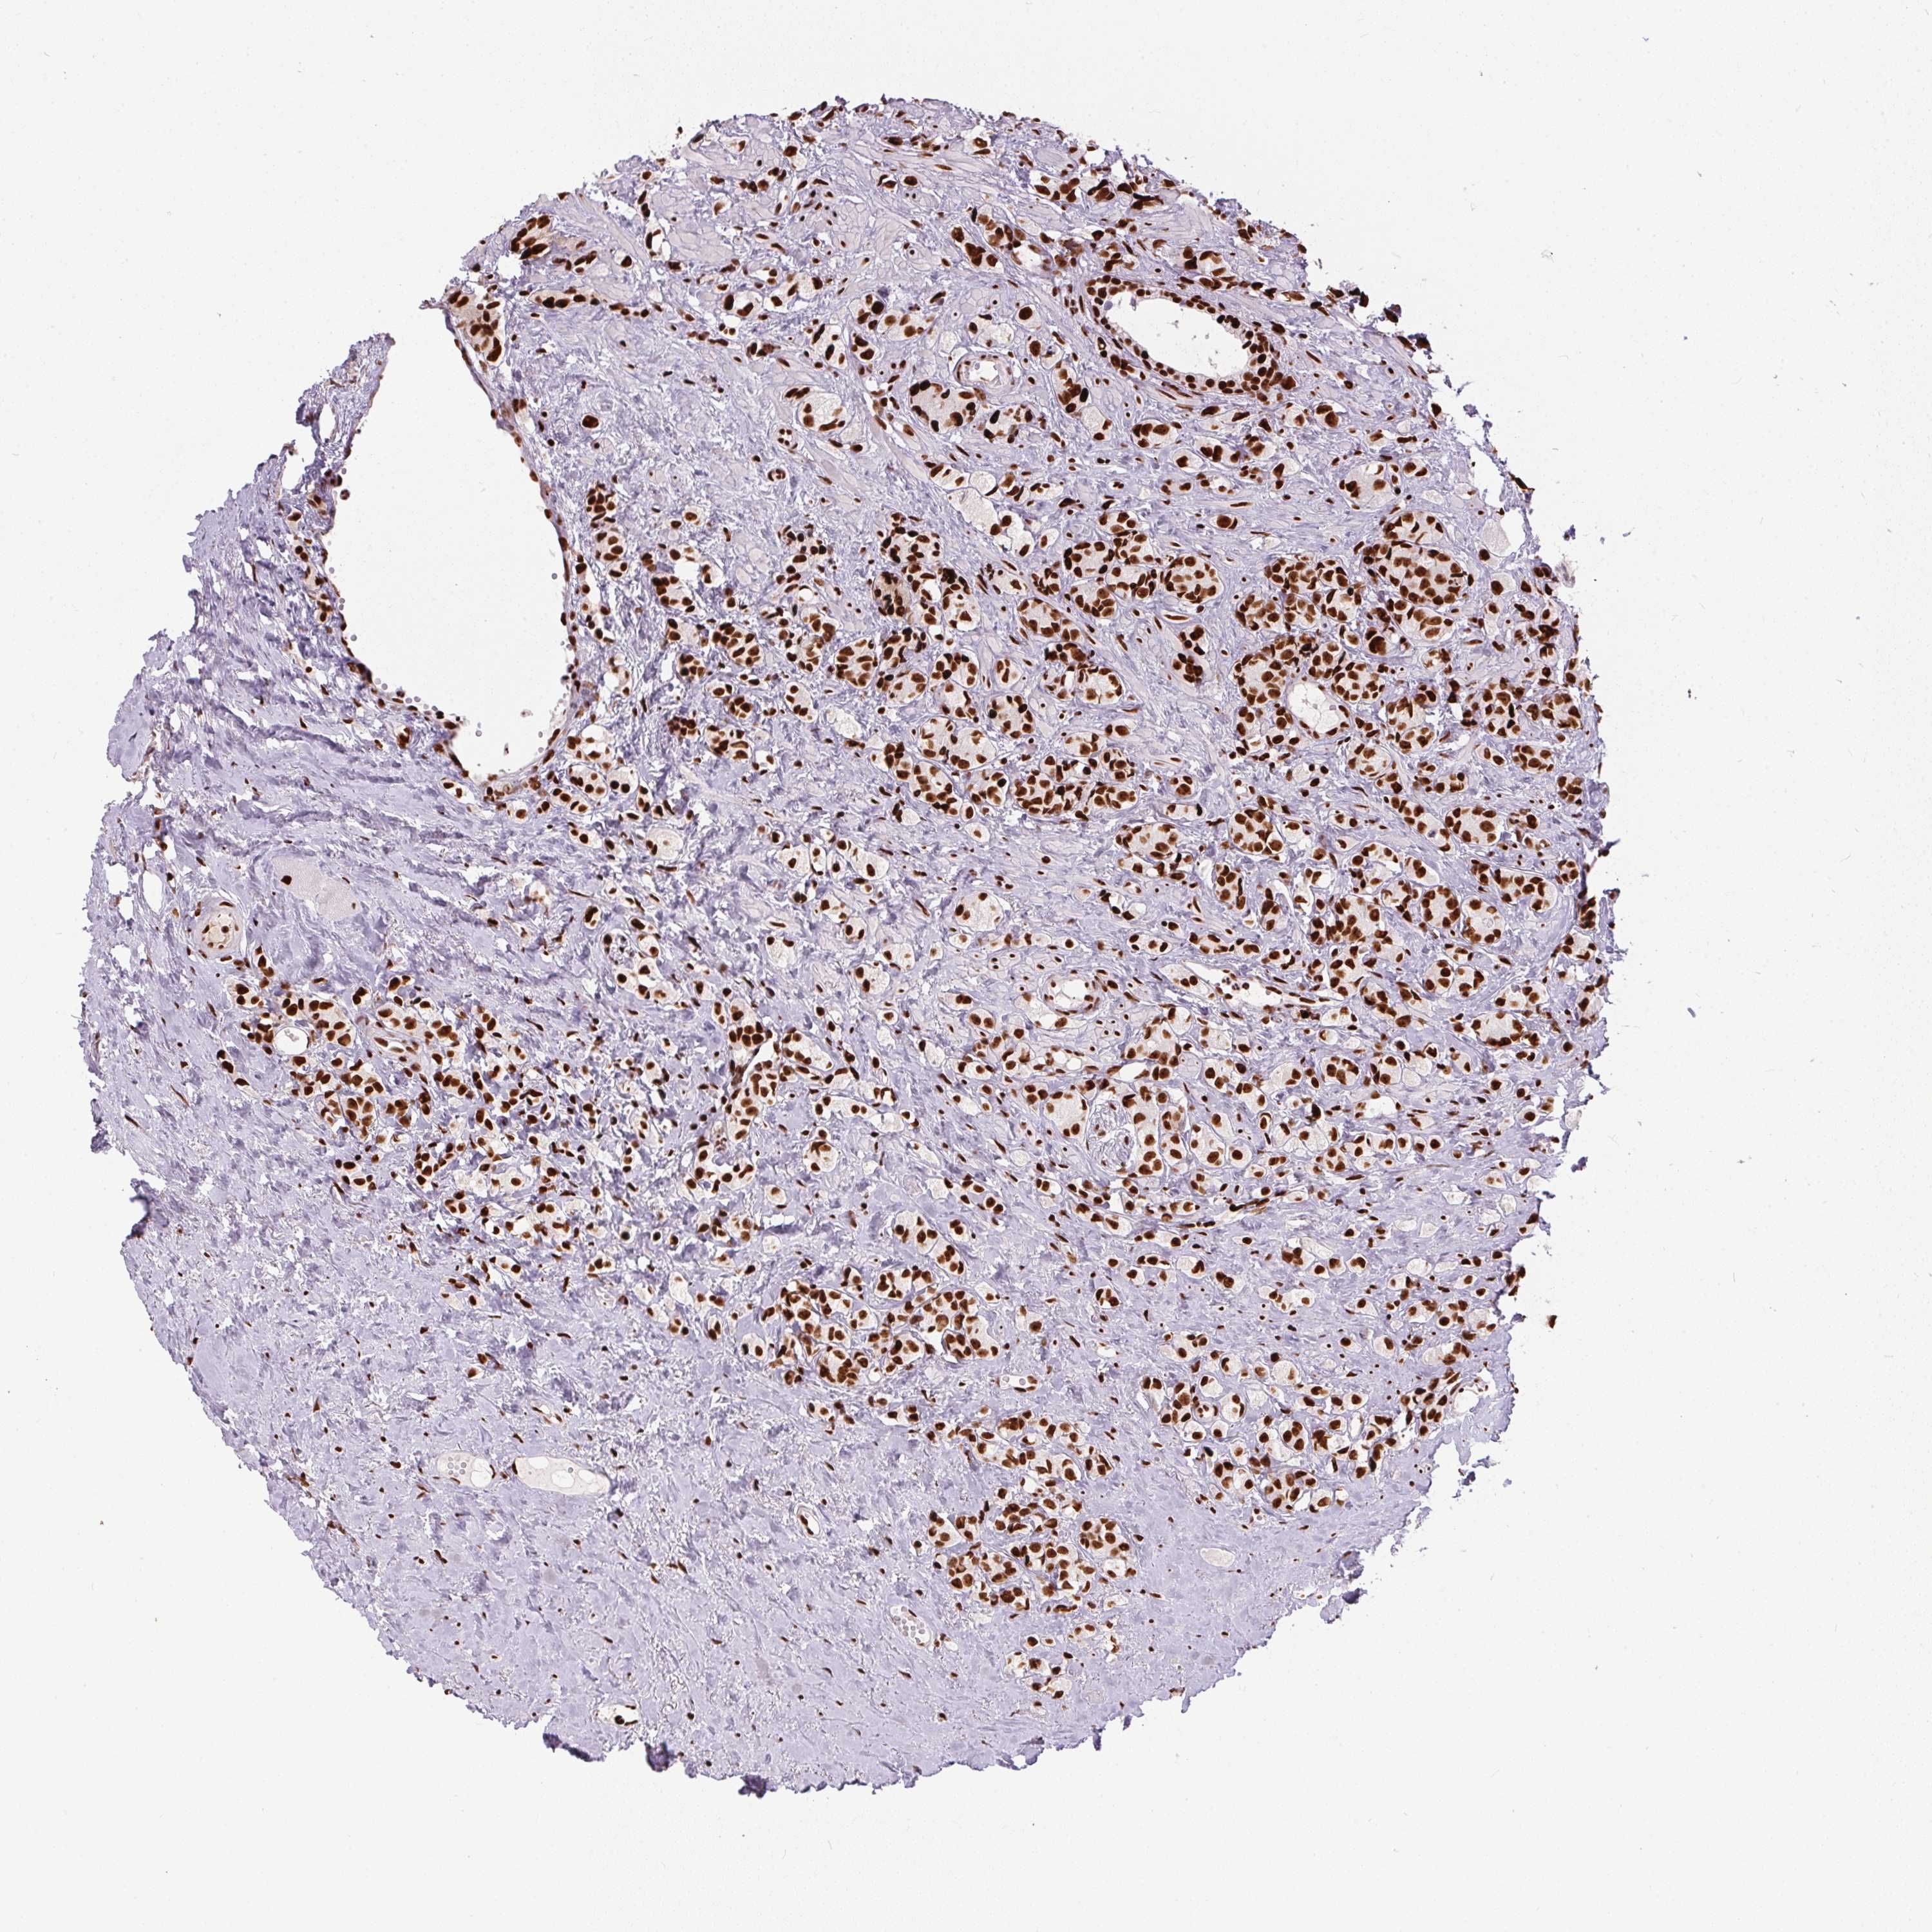

PROSTATE CANCER - Protein expressioni

A mouse-over function shows sample information and annotation data. Click on an image to view it in a full screen mode. Samples can be filtered based on level of antibody staining by selecting one or several of the following categories: high, medium, low and not detected. The assay and annotation is described here.

Note that samples used for immunohistochemistry by the Human Protein Atlas do not correspond to samples in the TCGA dataset.

Antibody stainingi

Antibody staining in the annotated cell types in the current human tissue is reported as not detected, low, medium, or high, based on conventional immunohistochemistry profiling in selected tissues. This score is based on the combination of the staining intensity and fraction of stained cells.

Each image is clickable and will lead to virtual microscopy that enables deeper exploration of all samples and also displays staining intensity scores, fraction scores and subcellular localization as well as patient and tissue information for each sample.

Antibody HPA062248

Staining

High

Medium

Low

Not detected

Intensity

Strong

Moderate

Weak

Negative

Quantity

>75%

75%-25%

<25%

None

Location

Nuclear

Cytoplasmic/membranous

Cytoplasmic/membranous,nuclear

Adenocarcinoma, High grade

Adenocarcinoma, NOS

Adenocarcinoma, Low grade